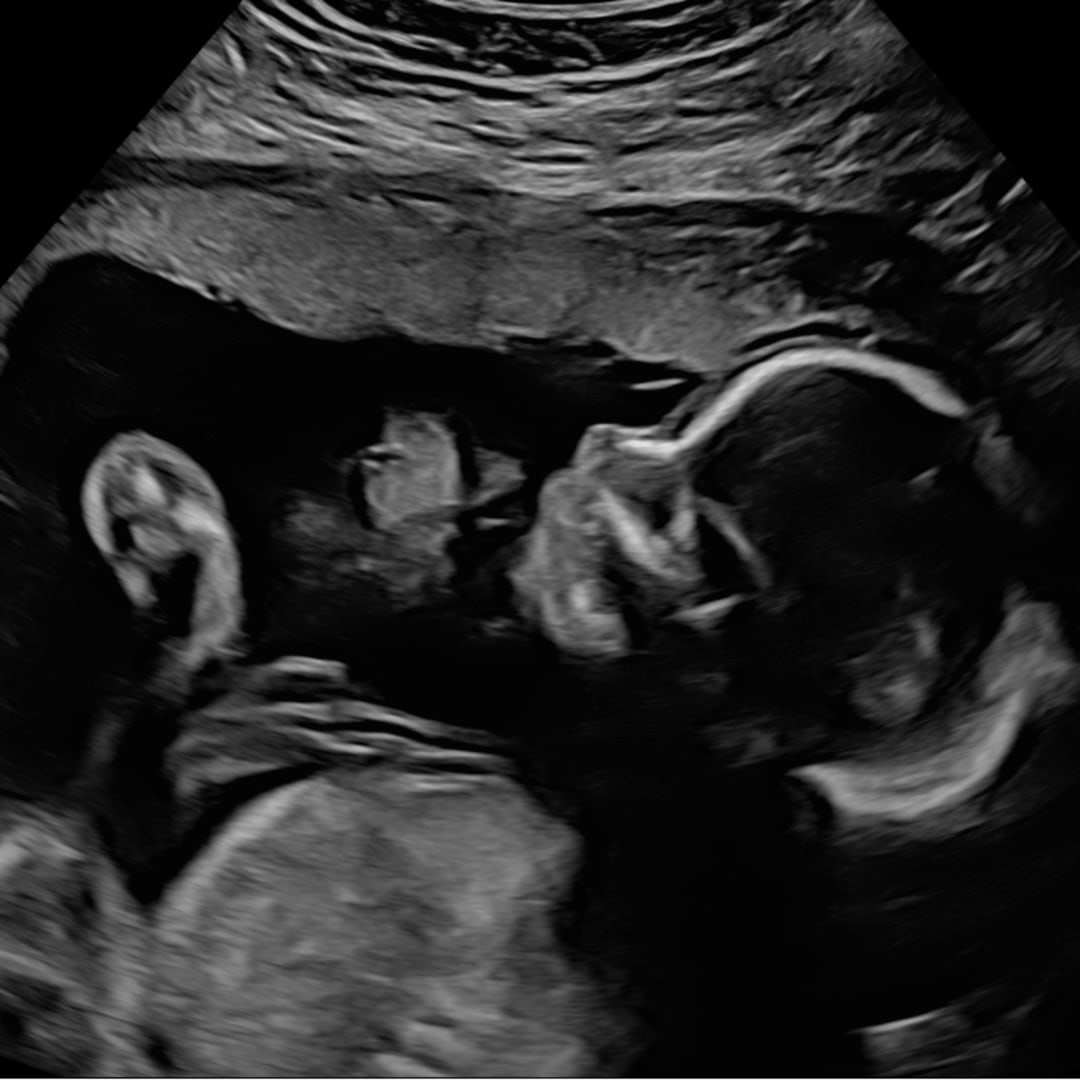

Baby Violet🩷🧸